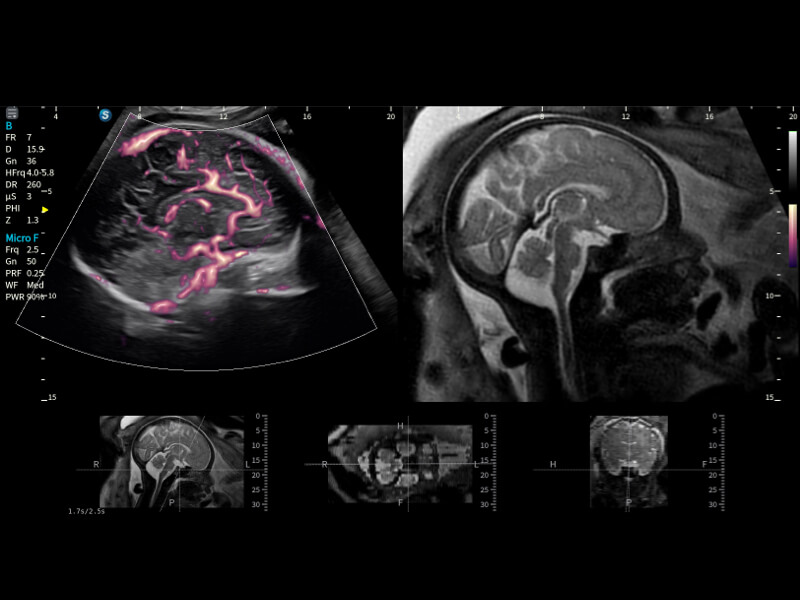

通過(guò)創(chuàng)新的Matrix E自適應(yīng)濾波算法,能有效濾除軟組織和噪聲信號(hào),最大限度保留超低速微細(xì)血流的信號(hào);結(jié)合超長(zhǎng)時(shí)間域算法,極大提升細(xì)微血流的敏感性和空間分辨率,更真實(shí)的反應(yīng)組織、包塊的血流灌注情況。

作為開(kāi)立醫(yī)療全新打造的超高端旗艦超聲產(chǎn)品,從探頭抬起喚醒開(kāi)啟掃查到多維探頭發(fā)射接收,通過(guò)先進(jìn)的場(chǎng)成像發(fā)射、自適應(yīng)聚合重建等技術(shù),基于RF Data原始射頻數(shù)據(jù)在圖像生成、高端功能等方面實(shí)現(xiàn)突破,為婦產(chǎn)科、兒科提供全方位臨床解決方案。

夢(mèng)溪?P80以“關(guān)愛(ài)女性”為基石,提供全方位的解決方案,量身定制以滿足女性的健康需求,涵蓋婦科、生殖健康檢查、產(chǎn)前篩查及產(chǎn)后康復(fù)等領(lǐng)域。